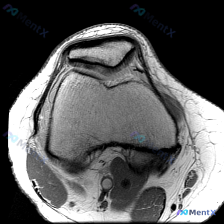

今天看到一个很有代表性的读片问题,整理出来和大家分享讨论:问题是判断这张髌股关节轴位T1加权MRI上有没有软骨异常,我们一步步梳理思路。 一、先看影像基本信息 这是一张膝关节MRI的轴位T1加权图像,扫描层面位于膝关节上方的髌股关节层面: 1. 骨骼结构:髌骨位于前方,骨皮质边缘清晰,骨髓脂肪信号正...

看到这个挺有代表性的读片病例,整理一下资料和分析思路分享给大家。 病例基础信息 这是一份单张膝关节MRI轴位T1加权序列影像,临床怀疑存在软骨异常,要求读片分析。 影像学读片结果 解剖结构评估 1. 骨性结构:髌骨形态完整,皮质连续,骨髓信号无异常;髌股关节对合关系大致正常,无半脱位;股骨远端滑车区...

今天遇到一个有意思的读片问题:只给了一张膝关节轴位MRI,问这里有没有软骨异常,整理一下分析思路分享给大家。 基本病例/影像信息 提供的是膝关节单张轴位MRI扫描图像,可识别的解剖结构包括:前方的髌骨、中部的股骨内外侧髁与髁间窝、髌股关节间隙,以及周围部分软组织。 客观影像所见 1. 软骨结构:髌骨...

看到一个很有讨论意义的膝关节影像病例,整理出来和大家分享一下。 病例基本信息 核心问题:临床怀疑存在膝关节软骨异常,仅提供单张膝关节MRI T1序列轴位影像进行分析。 影像学读片结果 这张影像为髌股关节层面的轴位T1加权像,读片结果如下: 1. 骨骼结构:髌骨、股骨内外侧髁形态完整,皮质骨连续,松质...

最近遇到一个有意思的读片病例:临床怀疑髌股关节软骨异常,但给出的单张T1加权轴位MRI却没看到明确病灶,整理一下整个分析思路分享给大家。 一、病例影像基础信息 这是一份膝关节MRI检查的T1加权轴位(横断面)图像,扫描层面位于髌股关节水平,先整理一下基础读片结果: 1. 解剖结构确认:前方为髌骨,后...